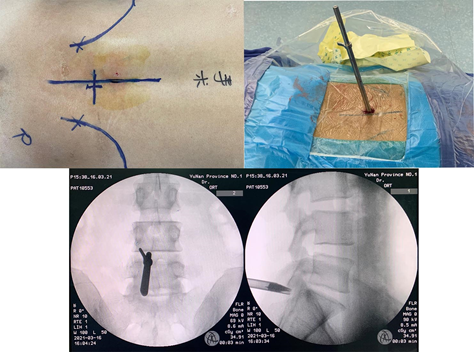

麻醉成功后医生和护士会将患者摆放成俯卧位,在C臂透视辅助下进行腰5骶1椎板间隙的穿刺定位,定位准确后沿着导丝经椎板间隙放入扩张管道,这种逐级扩张的操作对于肌肉的损伤很小、出血也很少,同时经椎板间隙入路也不需要切除正常的骨质;